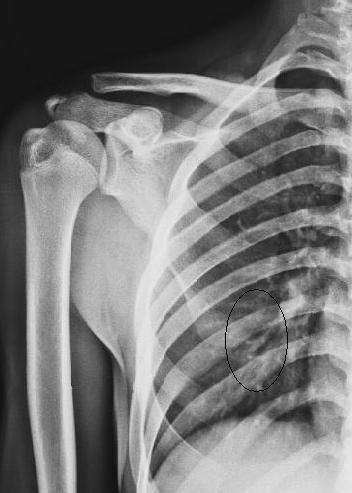

标题: X4242结果右肩胛骨下角骨折 [打印本页]

标题: X4242结果右肩胛骨下角骨折

右肩胛骨下角骨折。

如果照个肩胛骨侧位就好了,

开始我发了正常报告,结合侧位透视才发现骨折!如果是自己亲自照就好了,那匪徒的刀法太好了,砍的太整齐。

刀法不只是好,简直堪称绝妙,若非有透视,我绝认为是肺纹.

同志们!老师们!这个病例的确太难了,真的很像肺纹理。我第一次还下正常报告,幸运还没发出去啊!透视了才下骨折。

这绝对是骨折!

诊断这种片子,只有结合临床。

难以诊断。要拍侧位片。

正位片说明不了什么问题